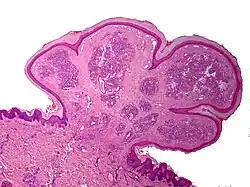

One study has suggested a correlation between pyogenic granulomas and Bartonella seropositivity.[9] However, this association has been questioned by others.[10] The microscopic appearance of a pyogenic granuloma consists of highly vascular granulation tissue. Inflammation is present. The lesion may have a fibrous character if it is older, and the surface may have ulcerations. Pyogenic granulomas rarely occur in the conjunctiva, cornea, or connective tissue of the eye following minor local trauma. Grossly, these mass lesions resemble those occurring at more common sites. The relationship of these lesions to lobular capillary hemangiomas of skin and oropharyngeal mucosa commonly referred to as pyogenic granuloma is uncertain.

Histopathological examination shows multiple capillaries (due to the vascular nature of the tumor), neutrophils (pyogenic), and necrotic tissue.